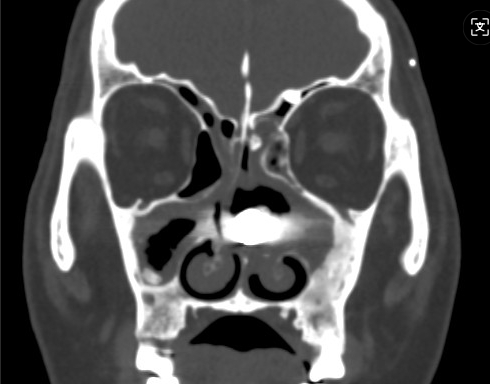

CT检查印证了推断:左侧鼻腔内果然有一高密度异物!